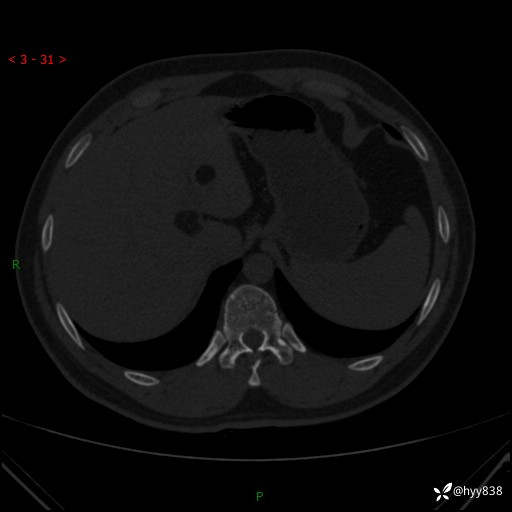

患者性别:男

患者年龄:28岁

简要病史:右肾肿瘤术后,常规复查

辅助检查:CT

临床诊断:右肾肿瘤术后

腹部CT+颅脑CT平扫